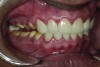

Figure 3. Preoperative 1:2 retracted right lateral view.

Figure 3

Figure 4. Preoperative 1:2 retracted left lateral view.

Figure 4

A thorough clinical examination and analysis were carried out to assess the esthetic and functional problems of the patient (Figure 2 through Figure 7). The medical history was non-contributory, except for mild leukoderma. Temporomandibular joint (TMJ) function was within normal range.